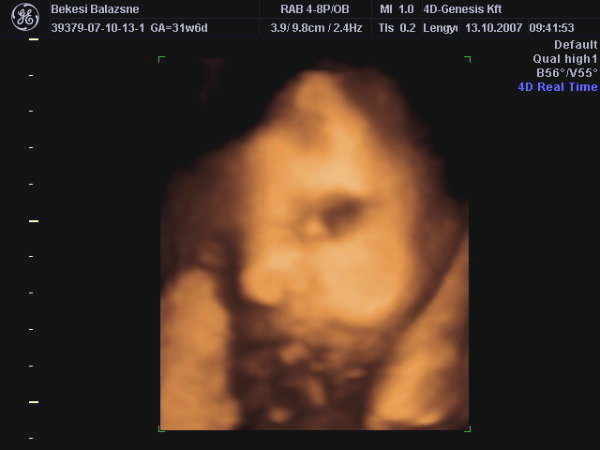

A második képen nyitva van a szeme is